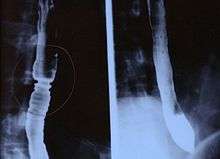

Endoscopically, ridges, furrows, or rings may be seen in the esophageal wall. Sometimes, multiple rings may occur in the esophagus, leading to the term "corrugated esophagus" or "feline esophagus" due to similarity of the rings to the cat esophagus. Presence of white exudates in esophagus is also suggestive of the diagnosis.[6] On biopsy taken at the time of endoscopy, numerous eosinophils can be seen in the superficial epithelium. A minimum of 15 eosinophils per high-power field are required to make the diagnosis. Eosinophilic inflammation is not limited to the esophagus alone, and does extend through the whole gastrointestinal tract. Profoundly degranulated eosinophils may also be present, as may microabcesses and an expansion of the basal layer.[1][4]

Radiologically, the term "ringed esophagus" has been used for the appearance of eosinophilic esophagitis on barium swallow studies to contrast with the appearance of transient transverse folds sometimes seen with esophageal reflux (termed "feline esophagus").[7]